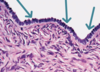

Endocrine gland cell

-> are close to capillaries

Which cell?

Simple alveolar cell

Name the classification of the following tissue:

Epithelial tissue.